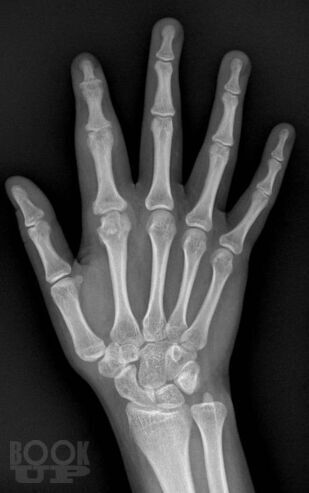

В учебном пособии представлены основные сведения о ревматологических заболеваниях, которые протекают с поражением суставов кисти, подробно изложена их рентгенологическая семиотика, описаны диагностические возможности других методов лучевой диагностики, таких как ультразвуковая диагностика, магнитно-резонансная и компьютерная томография. Особое внимание уделено дифференциальной диагностике заболеваний кисти.